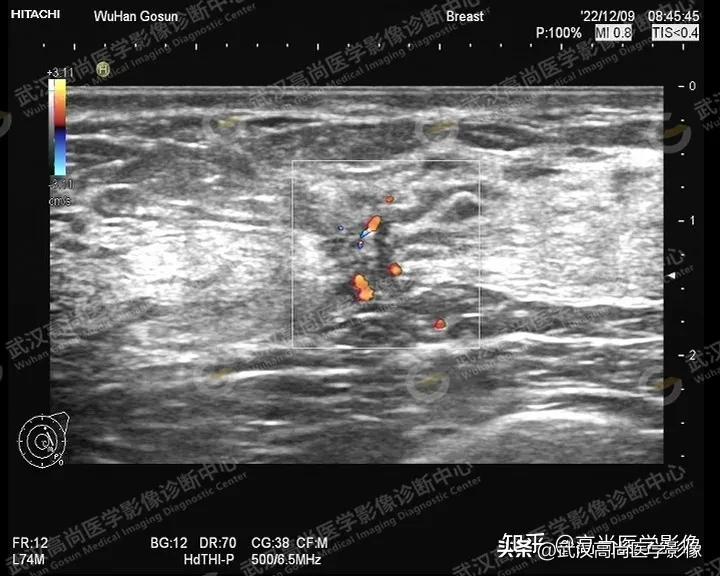

图一、图二、图三:右侧乳腺10点钟方向实性肿块,形态不规则,轮廓不规整,成角,大小约33x24x28mm,内部回声不均匀,内部见散在点状钙化,内血流信号丰富。